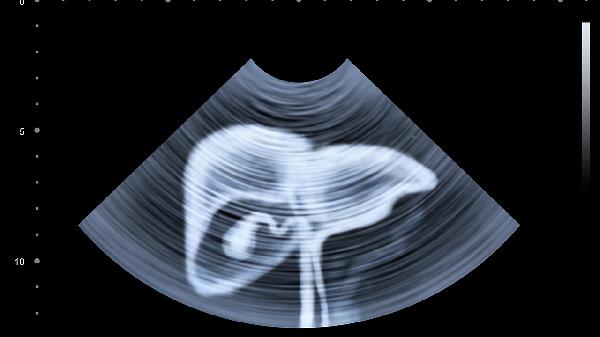

脾脏肿大可导致左上腹闷胀感,常见于传染性单核细胞增多症或血液系统疾病。脾梗死会引发突发性锐痛,伴随左侧肩部牵涉痛。脾脏外伤后包膜下血肿可能表现为渐进性胀痛。腹部超声或CT能准确评估脾脏形态。